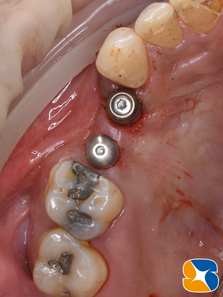

「忙しくてなかなか治療に来れない。」ということで、今回は歯茎を縫い合わせない方法(切開しない)でインプラントを移植しました。

骨を造成したところに上手くインプラントが移植されています。

使用インプラント:ノーベルバイオケア社製の パラレルCC とアクティブ。共に 直径4.2㎜、長さ10㎜。